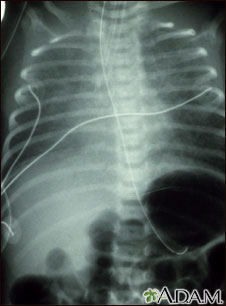

El retorno venoso pulmonar anómalo total es un tipo de enfermedad cardíaca congénita. Esta radiografía muestra un aumento de tamaño del corazón, del hígado y de los vasos sanguíneos pulmonares (vascularidad pulmonar).